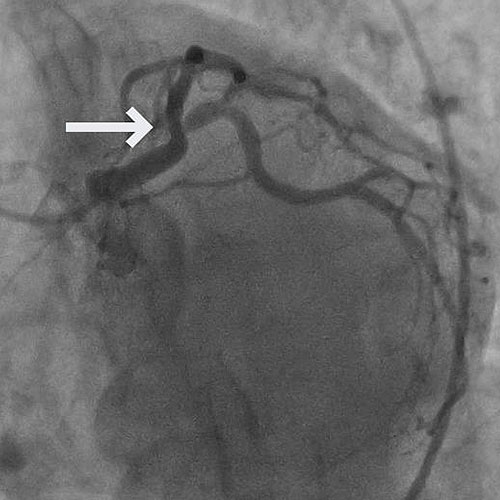

A 52-year-old male with a history of CAD, status post PCI to the mid left anterior descending artery (mLAD), presented with Canadian Cardiovascular Society (CCS) Class IV angina.